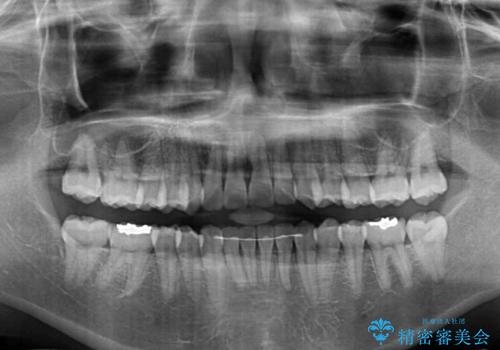

骨格的な問題を抱えた左奥以外は比較的早く咬み合わせが改善しましたが、左奥はどこで咬み合えば良いのか分からず、大変不便な思いをされていました。

ゴムかけにご協力いただき、最終的には反対咬合を改善することができ、患者様には大変満足していただきました。